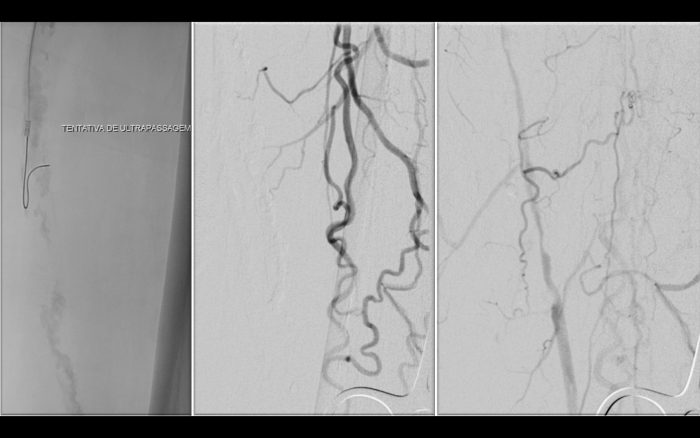

Paciente com história de claudicação dos membros inferiores para curtas distâncias, já submetido a angioplastia do membro inferior direito, retorna ao serviço com piora dos sintomas no lado esquerdo, sem lesão trófica (Rutherford 3)